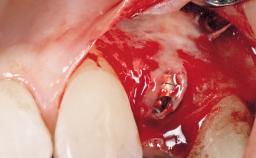

A 30-year-old female patient had lost tooth 21 and was referred to our clinic for consultation and treatment. Due to advanced apical infection, tooth 21 had been extracted two months earlier at another clinic and an acrylic-resin tooth had been bonded to the adjacent teeth. The patient desired implant treatment to avoid any damage to the adjacent natural teeth. While the patient had no history of any systemic disorder, she was a heavy smoker and exhibited medium to advanced periodontitis in the entire jaw. After the initial treatment to achieve a pocket probing depth of less than 4 mm and no bleeding on probing, a decrease in the height of the papillae mesial and distal to the extraction site and overall gingival recession were observed.

Type of Implants One-Piece|Reduced-Diameter

Bone Augmentation Horizontal|Staged

Augmentation Materials Autogenous chips|Membrane

Soft Tissue Grafting Simultaneous